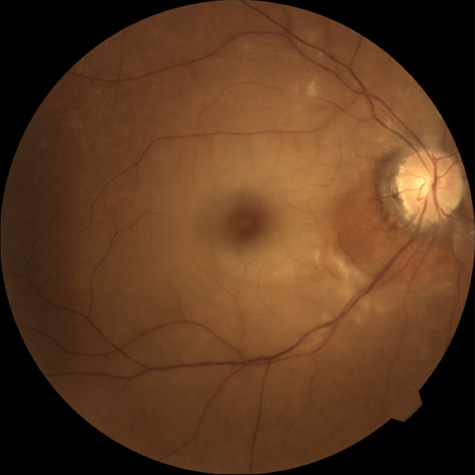

CILIORETINAL ARTERY OBSTRUCTION

Cilioretinal arteries can be selectively obstructed (Fig. 3). More commonly, however, they occur in association with central retinal vein obstruction.113 When they supply a significant portion of the macula, decreased visual acuity is common. Prognosis for visual outcome in such patients is good. Brown and co-workers114 studied 10 eyes having an isolated cilioretinal artery obstruction. Of those, 60% had an initial visual acuity of 20/40 or better and on follow-up examination, all eyes but one had a best-corrected visual acuity of 20/40 or better.114

Fig. 3. A: Cilioretinal artery obstruction showing opacity of the retina in the area of obstruction. B: The cilioretinal artery has begun to fill after the branches of the central retinal artery but is still not completely filled at this point in the angiogram.